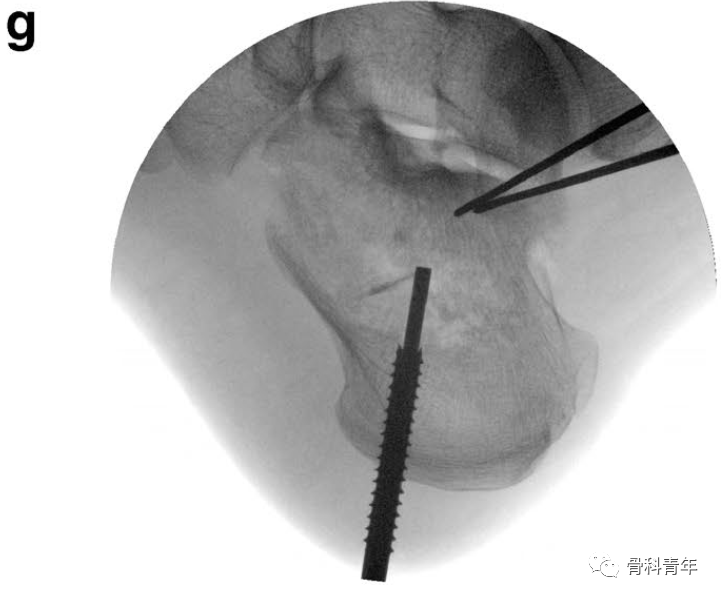

由于跟骨的解剖特点,跟骨骨折通常存在自外上至内下的斜行骨折线,形成载距突与跟骨后结节两个主要骨块,骨折移位导致距骨高度丢失、跟骨内翻。手术治疗的目标就是重建距下关节面匹配,纠正内翻,最终恢复跟骨高度与力线。

通过另一例跟骨后关节面压缩患者,可进一步理解该撑开器的复位作用:该患者后关节面压缩严重,跟骨高度丢失。

采用血管钳及克氏针撬拨,后关节面恢复有限,后关节面仍存在台阶(图中绿线所示)。

采用撑开器可实现后关节面的复位。